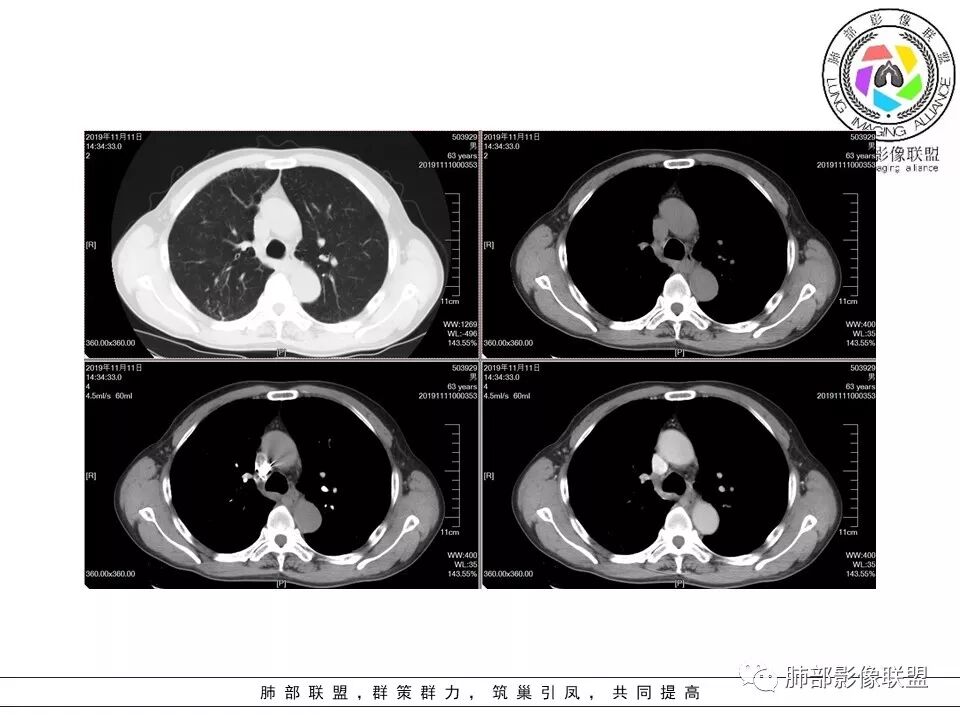

南边:类风湿性肺纤维化——NSIP

右上叶边缘收缩,宽基底与胸膜相连,胸膜增厚,附近索条,支持炎性

南边:糊墙,长轴与胸膜平行;边缘收缩+膨隆;脐凹征

常规:隐球菌与癌鉴别

脐凹征,高度提示恶性

因为其与胸膜的关系与右上叶的不一致,所以不能一元论

而且周围的表现不一致

还有就是间质性病变基础上,恶性变的几率很高

病理结果:巨细胞癌。